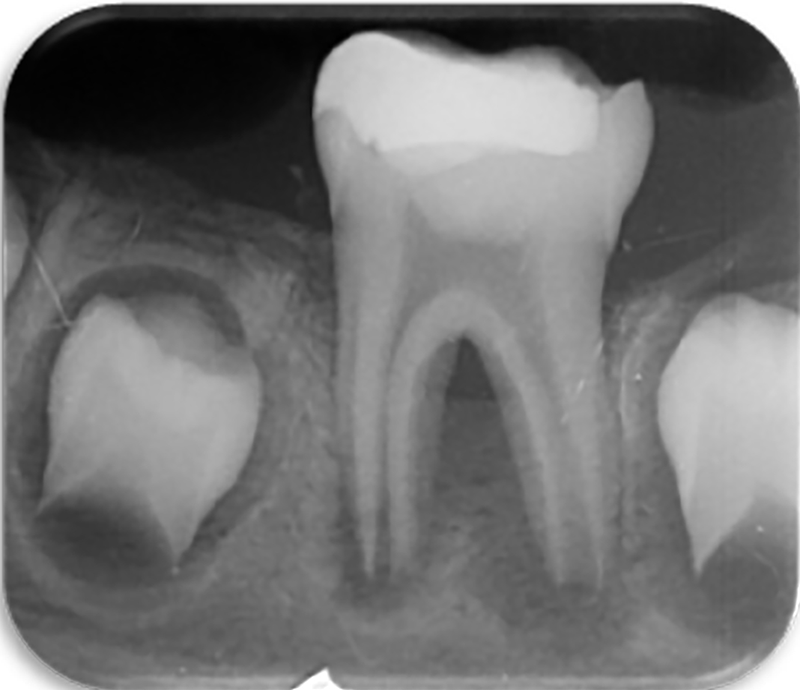

مشاهده موارد درمان شده به بیماران اطمینان میدهد که حتی دندانهای آسیبدیده و پیچیده نیز با درمان تخصصی قابل حفظ هستند. همچنین این بخش فرصتی برای همکاران دندانپزشک فراهم میکند تا با روند و نتایج درمانهای پیچیده آشنا شوند.

تشخیص دقیق و درمان استاندارد در اندودنتیکس بدون بهرهگیری از تکنولوژیهای روز دنیا امکانپذیر نیست. در این مرکز مجموعهای از تجهیزات مدرن بهکار گرفته شده است تا درمان در محیطی ایمن، کمدرد و با بالاترین دقت انجام شود. یکی از این امکانات، رادیوگرافی دیجیتال با دوز بسیار پایین اشعه است. این فناوری نسبت به رادیوگرافیهای قدیمی میزان اشعه را تا حد قابلتوجهی کاهش میدهد، در عین حال تصویری بسیار واضح و دقیق ارائه میکند. تصاویر دیجیتال بلافاصله قابل مشاهده هستند و امکان بزرگنمایی، بررسی ضایعات و ارزیابی طول کانال با دقت بالا را فراهم میکنند. برای بیمارانی که نگران درد تزریق هستند، بیحسی دیجیتال یک گزینه مناسب است؛ سیستمی که تزریق آن با کنترل کامپیوتری انجام میشود و به دلیل تنظیم دقیق فشار و حجم تزریق، یکی از کمدردترین روشهای بیحسی محسوب میشود. این تکنولوژی بهویژه برای بیماران مضطرب یا دندانهای با التهاب بالا بسیار مؤثر است. برای مرحله پرکردن کانال، از روش ترموپلاستیک سهبعدی استفاده میکنیم تا سیل دقیقتری در کانالها و انشعابات فرعی ایجاد شود. همچنین تمامی محلولهای شستشو با سیستمهای سونیک و اولتراسونیک فعالسازی میشوند؛ روشی که اثربخشی شستشو را چند برابر میکند و باعث حذف کاملتر باکتریها و دبریها میشود. این تکنولوژیها سهم بزرگی در موفقیت نهایی درمان و ماندگاری آن در بلندمدت دارند. استفاده از میکروسکوپ دندانپزشکی، رادیوگرافی دیجیتال کمدوز، بیحسی دیجیتال، تکنیکهای گرم برای پرکردن کانال، فعالسازی پیشرفته محلولهای شستشو و بسیاری از امکانات و تجهیزات تخصصی دیگر باعث شده است که درمانهای اندودنتیک در مطب دکتر سلطانی نژاد با بالاترین استانداردهای جهانی، بیشترین دقت و کمترین ناراحتی برای بیمار انجام شود.